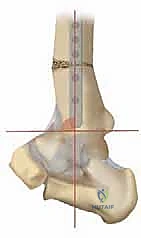

2. التصوير بالأشعة السينية بوضعية الوقوف (Weight-bearing X-rays)

هذا هو حجر الأساس في التشخيص. الأشعة العادية والمريض مستلقٍ لا تظهر الحجم الحقيقي للتشوه. يطلب الدكتور هطيف صوراً خاصة والمريض يحمل وزنه كاملاً على قدميه.

* المنظر الأمامي الخلفي (AP View): لتقييم المسافة المفصلية وتحديد زاوية سطح الساق (Tibial Anterior Surface Angle - TAS).

* منظر سالتزمان (Saltzman View): وهو منظر إشعاعي متخصص جداً لتقييم محاذاة الكعب الخلفي بالنسبة لمحور الساق، وهو أمر حاسم في التخطيط الجراحي.